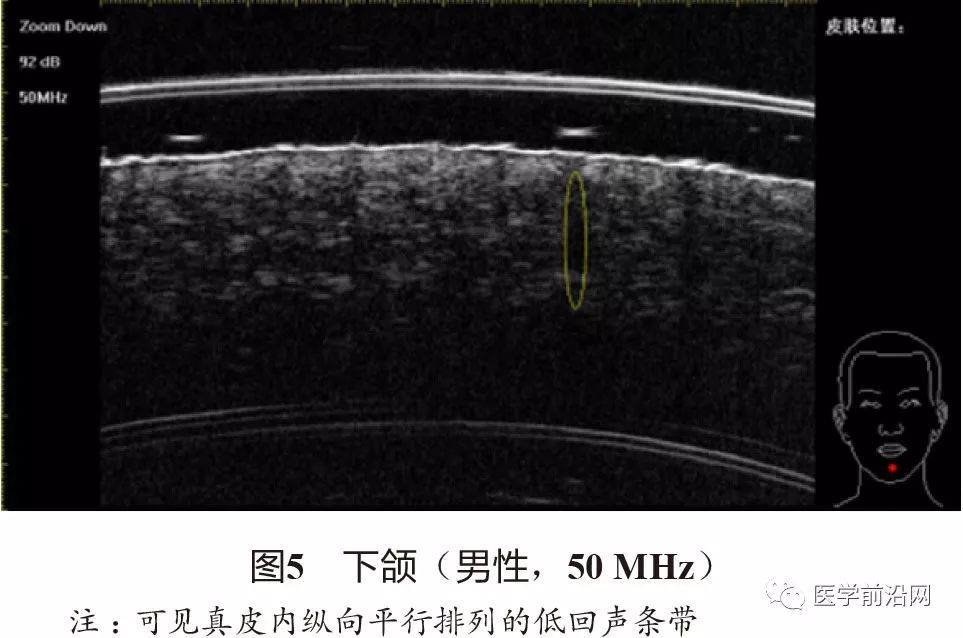

除皮肤层次外,部分皮肤附属器也可以在高频超声下清晰地观察到。在有终毛的区域(头皮、须毛、腋毛区),50~75 MHz超声可以观察到真皮内纵向平行排列的低回声条带(图5),对应毛囊结构。甲单位也可以在高频超声下很好地显示:甲板为两条纤细清晰的强回声带加中央的一条中低回声带,甲床为中等至低回声区域(图6)。在50~75 MHz超声下,甲板显示得更加清晰,而甲下常表现为声影(图7);在20~22 MHz超声下,甲床和甲母可以更完整地显示。